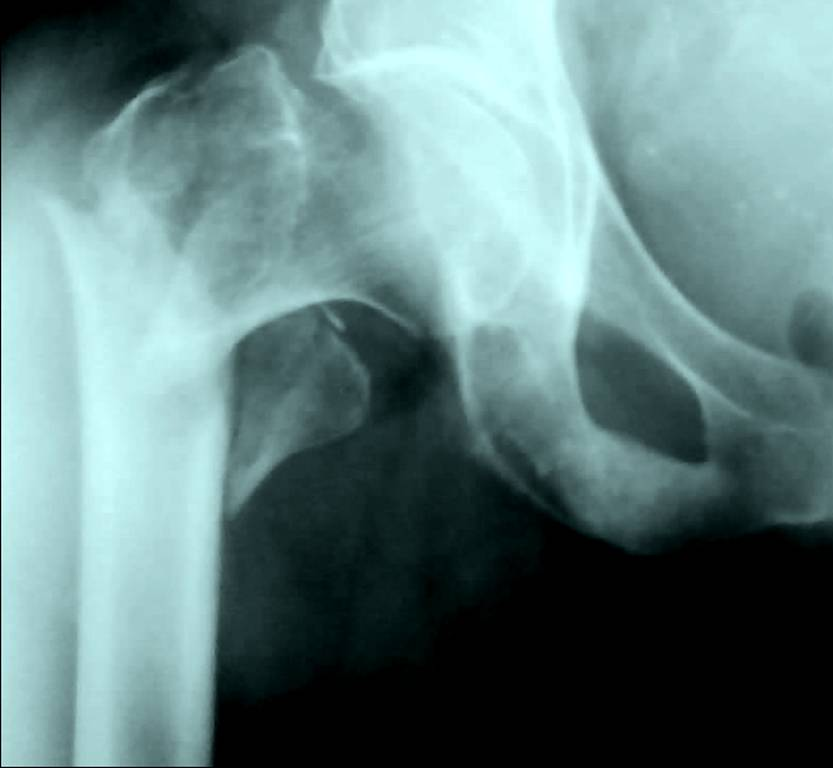

2. Left panel: right femoral head fracture and sclerotic metastasis of the pubic bone. On previous CT no metastasis was found in the femoral bone. Right panel: Fracture of the left clavicle in a man after falling off the bike.